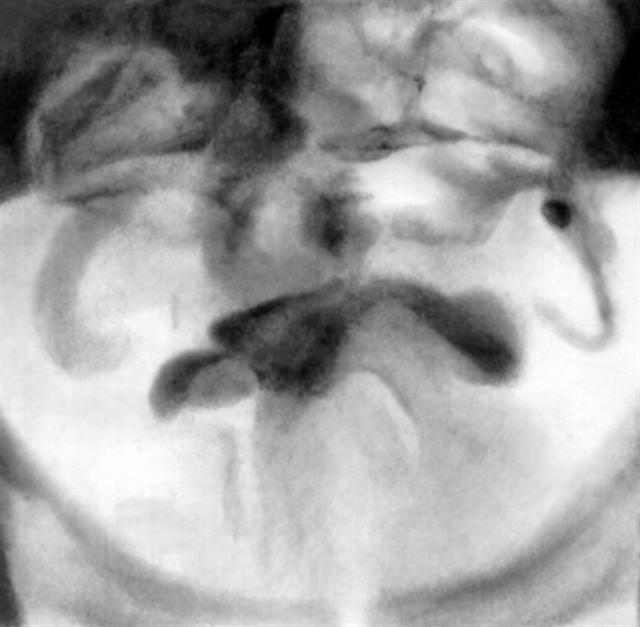

Рис. 2б). Цистограмма больных аденомой предстательной железы: два крупных конкремента.